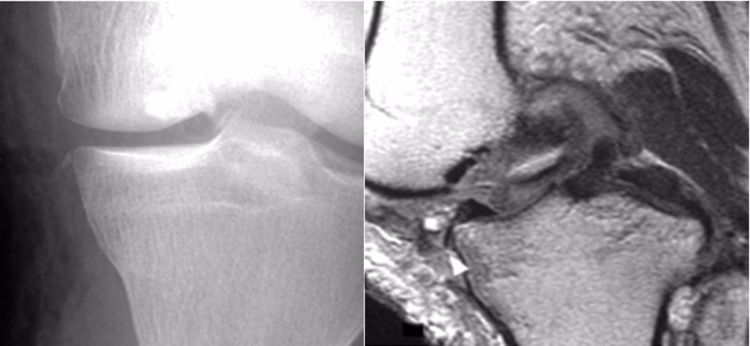

2.撕脱骨折:后交叉韧带胫骨附着点的撕脱骨折较常见。表现为胫骨平台后部有线形的T1加权低信号,T2加权,STIR高信号的骨折线,撕脱的碎片和后交叉韧带相连而韧带的连续性未见中断。

3.后抽屉征:因胫骨后沉引起,除非膝关节脱位,否则后移程度不重。

4.内侧胫骨平台撕脱骨折:胫骨平台前外侧撕脱骨折(Segond骨折)常常合并ACL损伤。而内侧胫骨平台骨折撕脱骨折则常常合并PCL损伤。